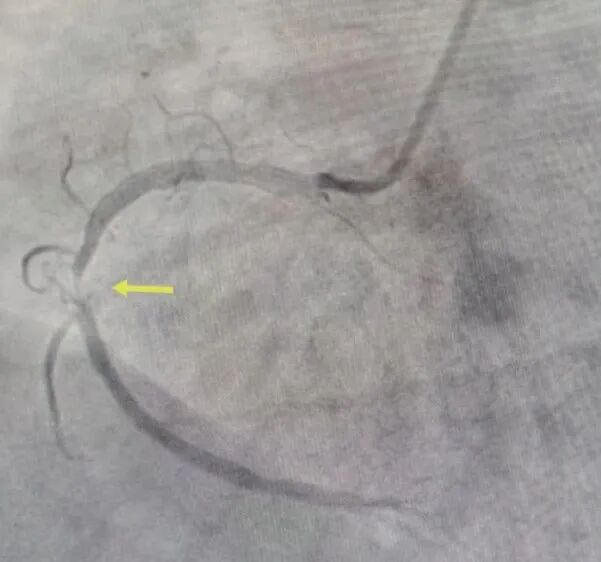

怎么确定是不是冠心病?

如何治疗冠心病?

在高血压、冠心病、心衰、心肌病等心血管疾病诊治方面具有丰富临床经验,擅长复杂冠脉血管介入治疗、心脏起搏器植入术、心律失常射频术。独立完成各项介入手术3000余例。